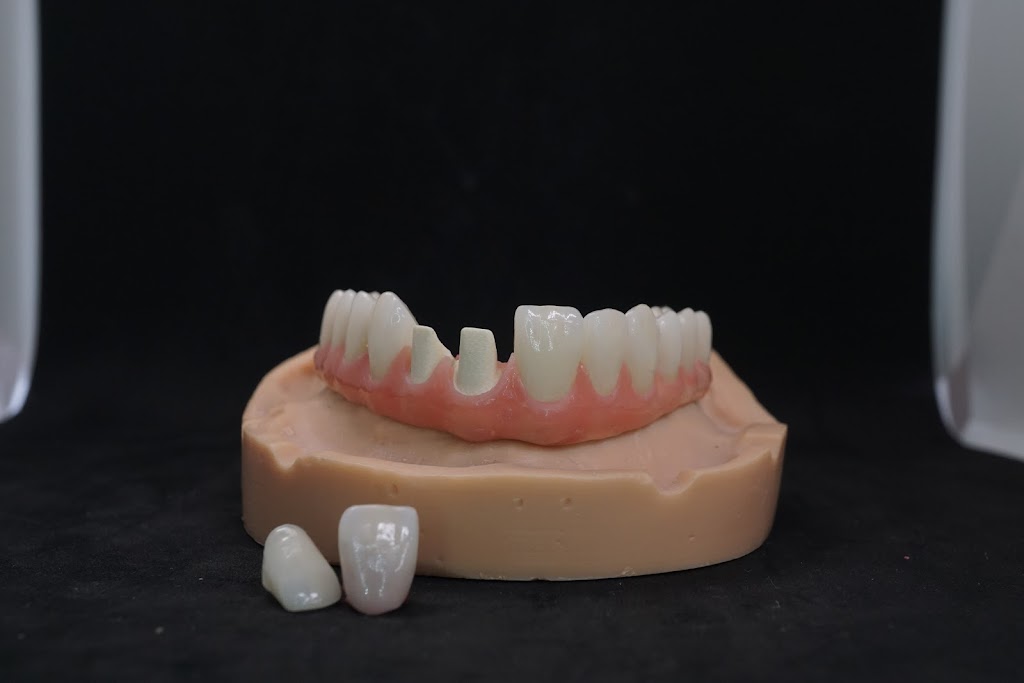

Photos of Smile Plus Dental Lab Inc